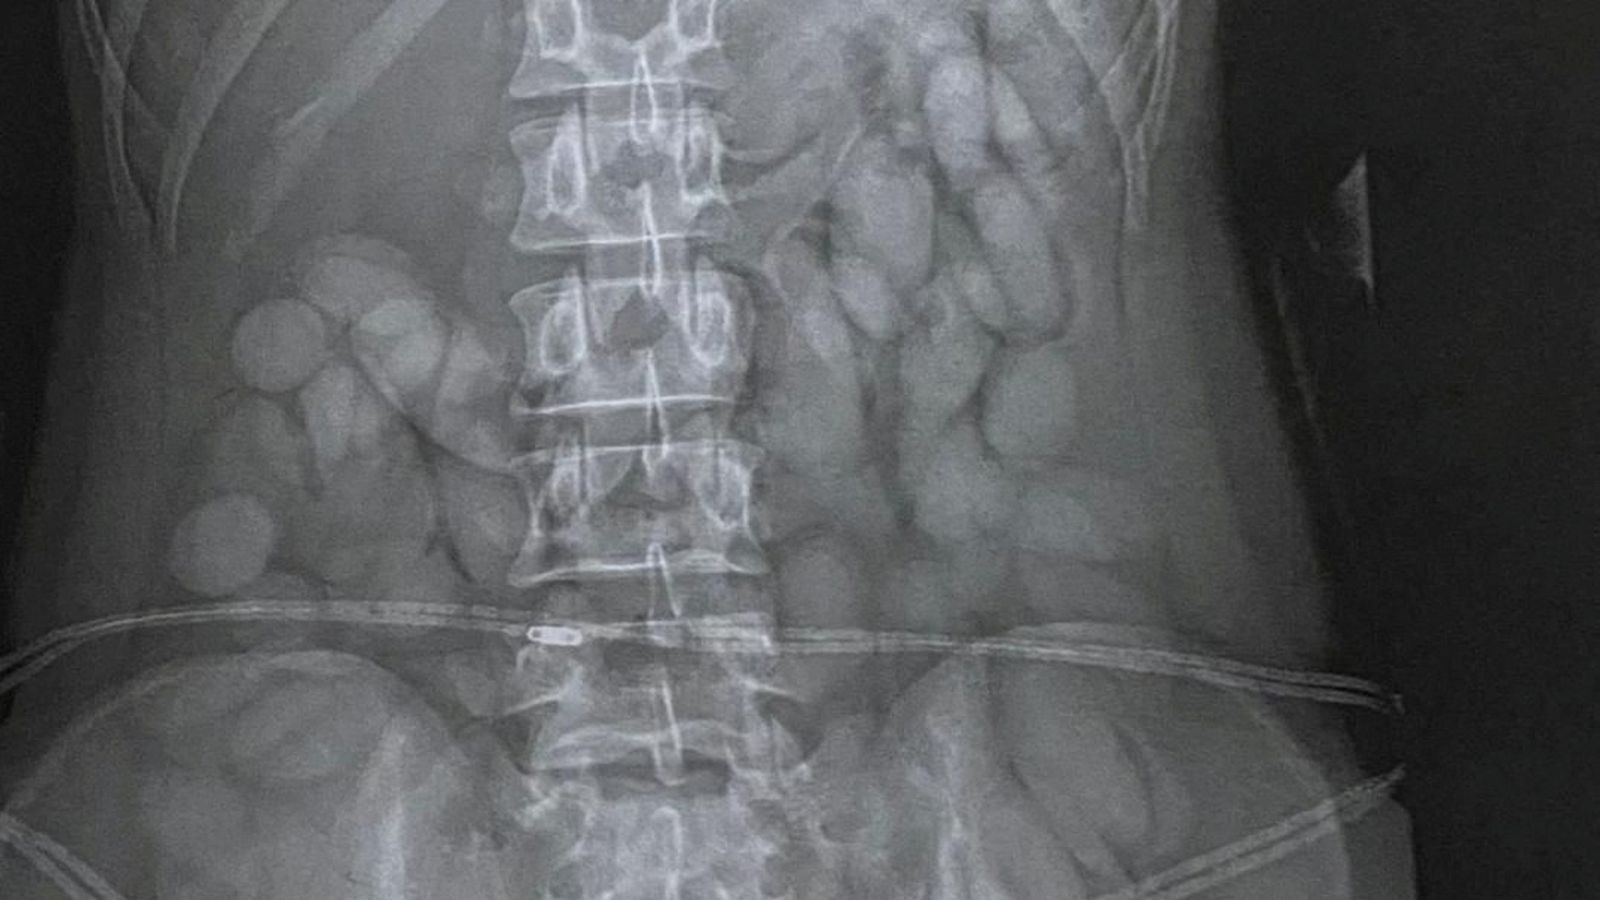

Pasi u arrestuar, gruaja u dërgua në spital, ku në rrezet X u vërejtën objekte të dyshimta në barkun e saj – që me gjasë i kishte gëlltitur qëllimshëm.

Nën vëzhgimin e policisë, ajo nxori nga goja 68 “plumba” me kokainë që peshon afro 850 gramë.